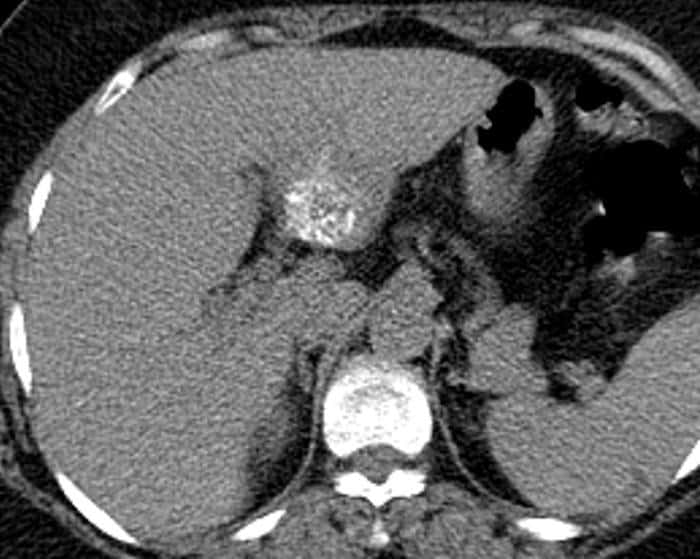

Ung thư đường mật

Ung thư đường mật - Ảnh 4

» Thông tin: Nữ giới – 56 tuổi.

» Lâm sàng: Viêm gan C.